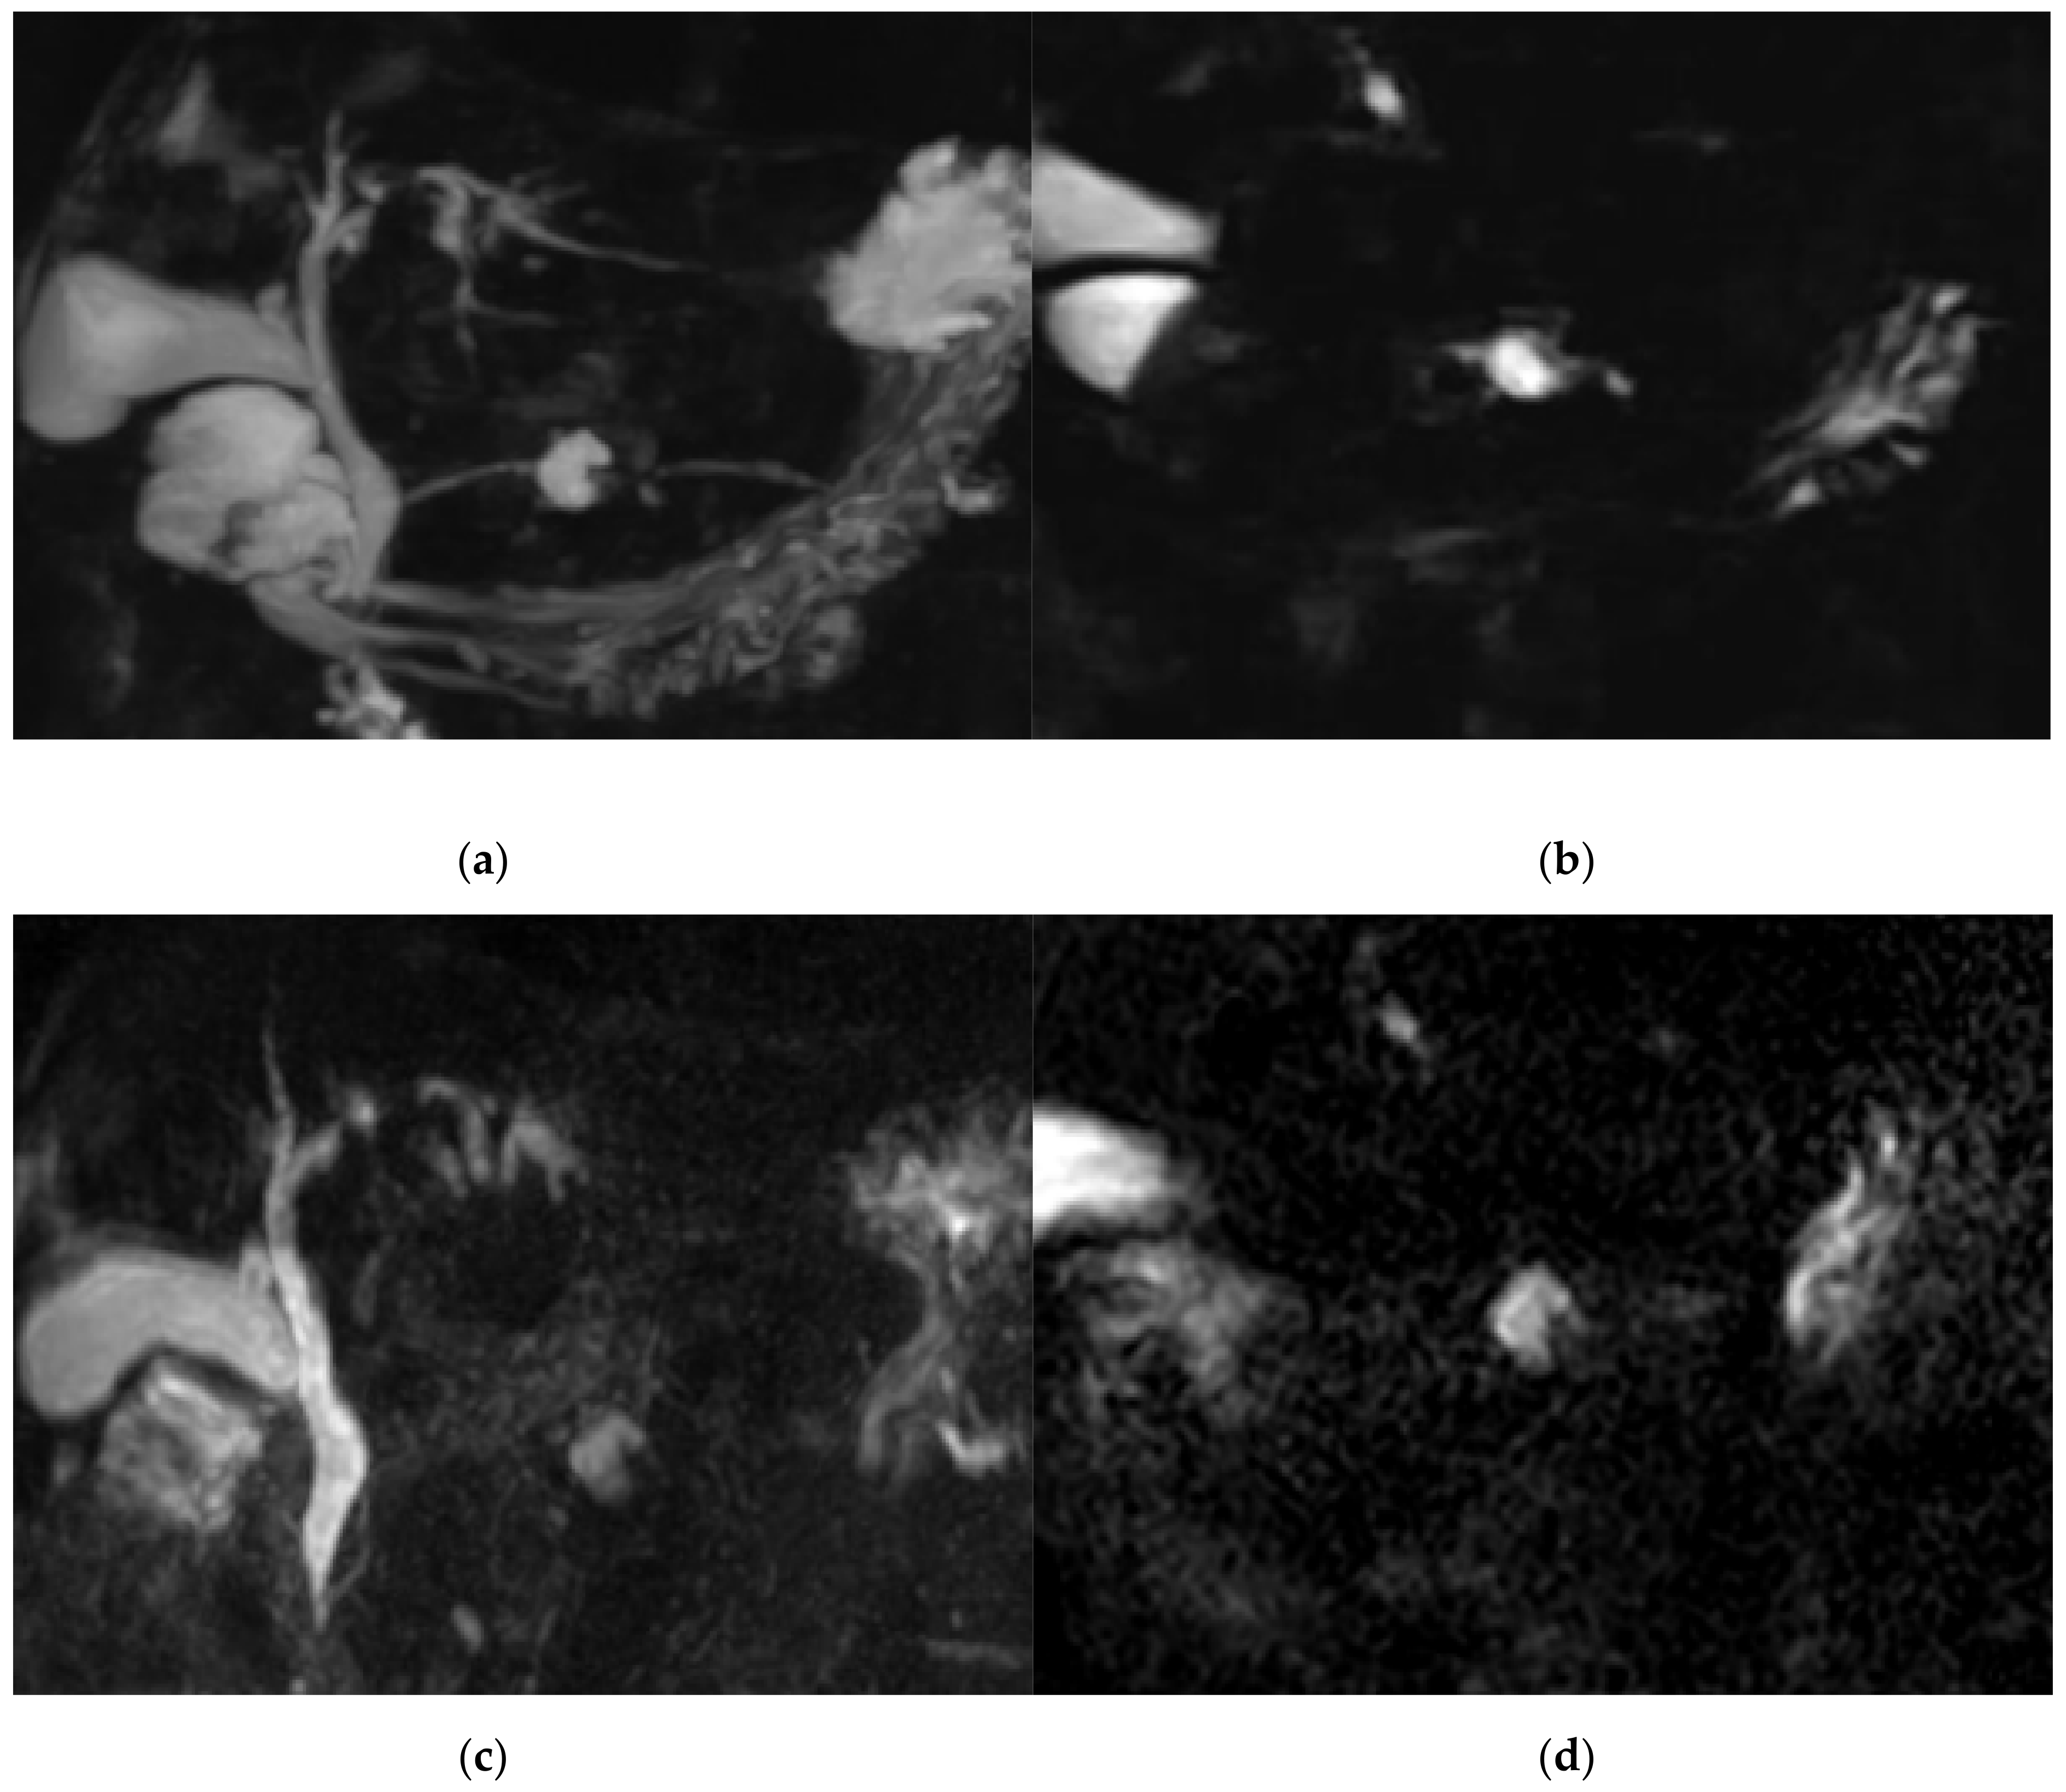

Figure 4. A 79-year-old female with BD-IPMN in pancreatic body. Communication between a cyst and proximal pancreatic duct (PD) was shown with BH-CS-MRCP in both the 3D (a) and source image (b), but not shown with BH-GRASE-MRCP in both the 3D (c) and source (d) image. Visualization of proximal PD (5 vs. 5, BH-CS-MRCP vs. BH-GRASE-MRCP, respectively), mid PD (4 vs. 1.7), and distal PD (4 vs. 1.7) were better with BH-CS-MRCP (a) than those with BH-GRASE-MRCP (c).

The score for image quality degradation by artifacts was significantly higher with BH-GRASE-MRCP than BH-CS-MRCP (4.86 ± 0.26 vs. 4.71 ± 0.42, p = 0.025). Background suppression, visualization of right and left 2nd level IHD, mid PD, and distal PD were significantly higher with BH-CS-MRCP than BH-GRASE-MRCP (p < 0.05, Table 2, Figure 2). However, overall image quality (p = 0.797), duct visualization of the CBD (p = 0.242), right (p = 0.589) and left 1st level IHD (p = 0.238), cystic duct (p = 0.089), and proximal PD (p = 0.643) did not show a significant difference between the imaging modalities (Figure 3). There were 24 patients with BD-IPMN who were considered to have communication between a cyst and the PD, while 21 patients (87.5%) on BH-CS-MRCP and 15 patients (62.5%) on BH-GRASE-MRCP demonstrated the presence of such communication (p = 0.07, Table 2, Figure 4).